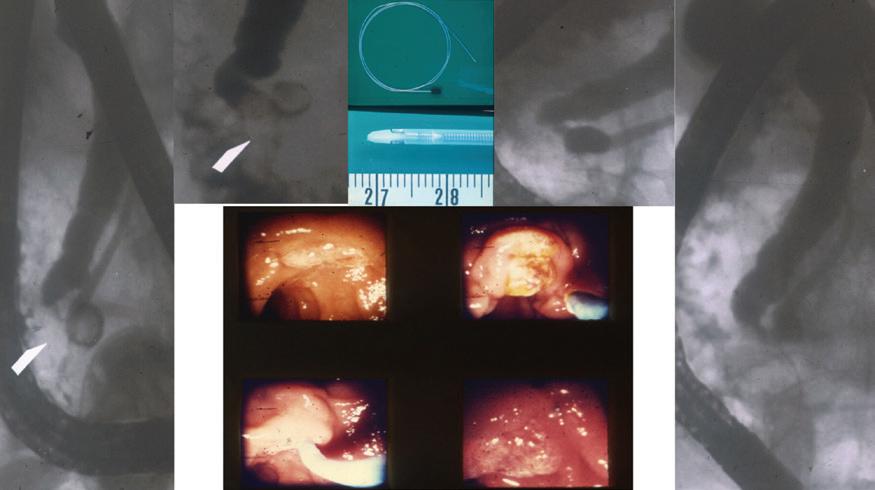

FIG 1.3 The endoscopic and fluoroscopic images from the first sphincterotomy performed by Drs. Nakajima and Kawai in Kyoto, Japan, in 1974. Clockwise from left: The fluoroscopic images on the left show the distal bile duct calculus (arrow) with upstream filling of the bile duct. The catheter was used for cannulation and sphincterotomy. On the right, the cholangiogram and pancreatogram revealing bile duct clear of filling defect.

FIG 1.4 ERCP-directed bile duct drainage using biliary stents was introduced by Soehendra and Reynders-Frederix from Hamburg, Germany, in 1979, adding to the armamentarium of therapeutic ERCP. The team used a 20-cm-long, 7-Fr radioopaque angiographic catheter with 12 side holes inserted over a guidewire with a single pigtail that allowed it to be fixed inside the bile duct. (Photo courtesy Dr. Peter Cotton, Medical University of South Carolina.)